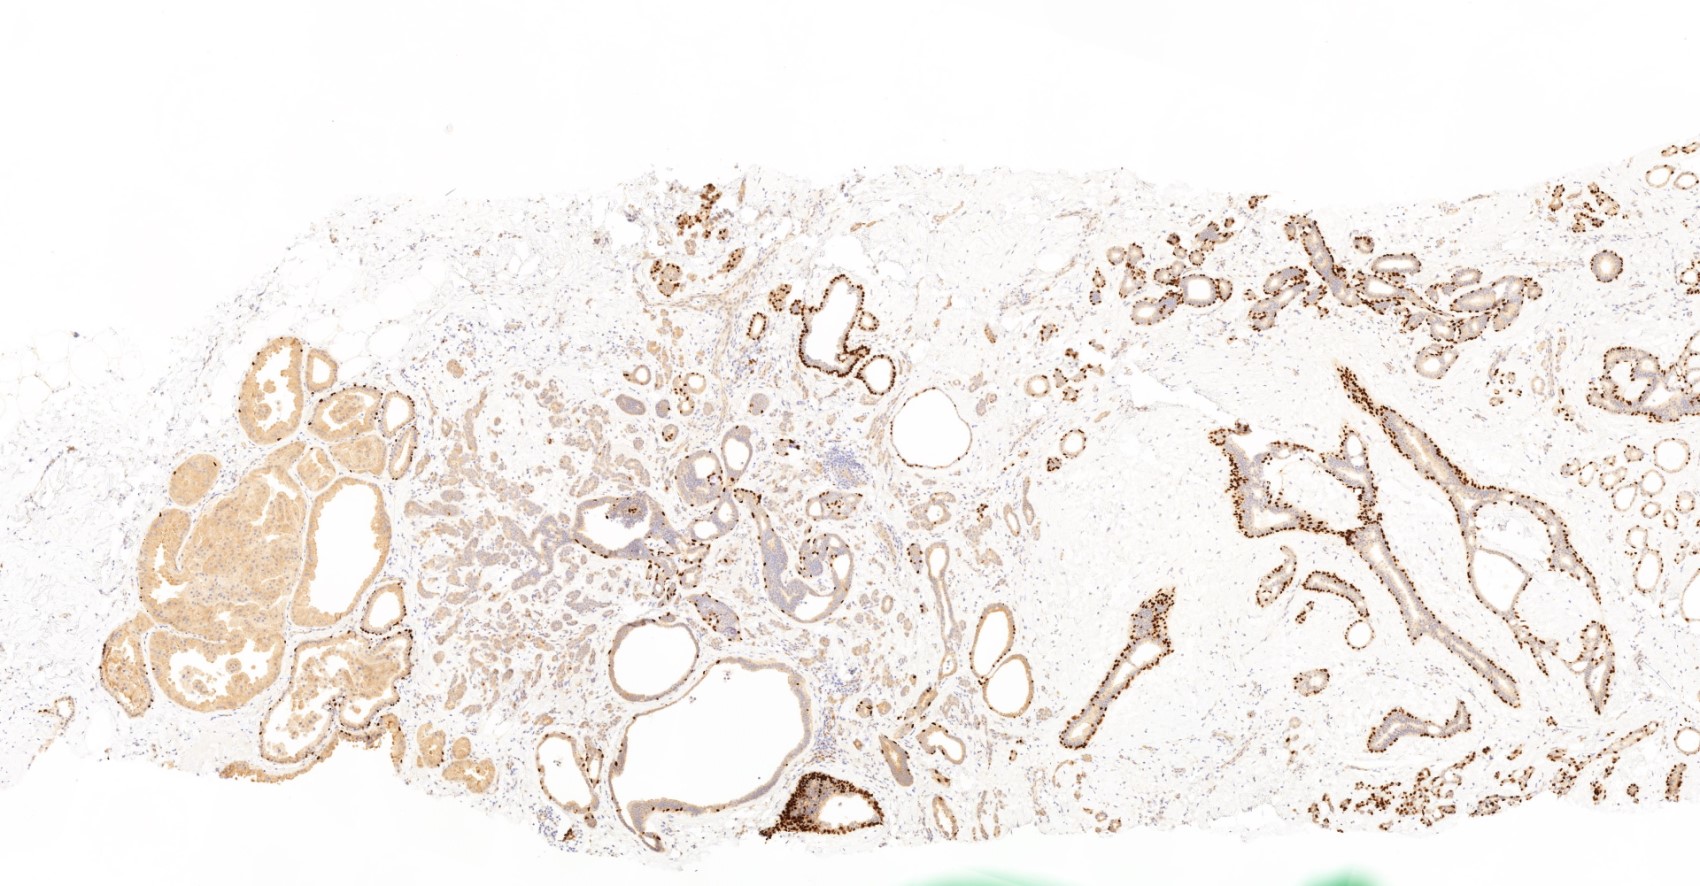

- No myoepithelial cell lining (as seen in DCIS or benign lesions)

- Angiolymphatic invasion in 35%; differs from tissue retraction because:

- Occurs outside margin of carcinoma

- Does not conform precisely to space it is in

- Endothelial lining is present and is CD31+, ERG, D2-40+, CD34+ and factor VIII+

Microscopic (histologic) images

Contributed by Julie M. Jorns, M.D., Kristen E. Muller, D.O., Gary Tozbikian, M.D. and Emad Rakha, M.D.

Positive stains

- Luminal low molecular weight cytokeratins (CK8 / 18, CK19 and CK7 and pancytokeratins such as AE1 / AE3, CAM 5.2, MNF-116), EMA, E-cadherin, p120, ER (60 - 80%), PR (50 - 70%), HER2 (15 - 20%) (Am J Clin Pathol 2006;125:377)

Negative stains

- CK20, CD34

- Myoepithelial markers: p63 (positive in benign lesions), CD10, calponin (Am J Surg Pathol 2001;25:1054, Mod Pathol 2002;15:397)